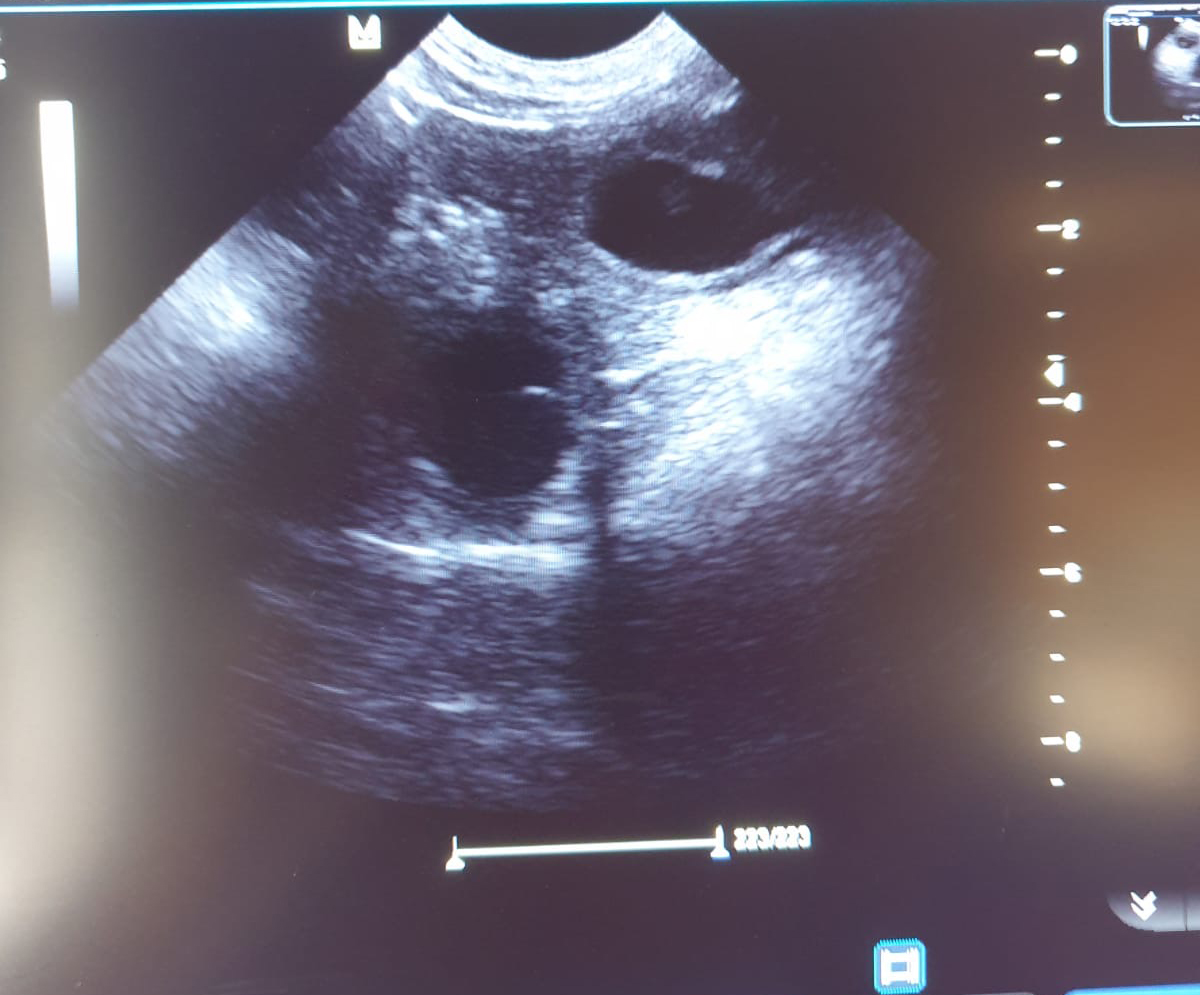

Heute war also der Tag der Tage. Der Tag an dem man Gewissheit bekommt, ob die Hündin aufgenommen hat oder nicht.

Auch wenn in den letzten Tagen einiges für eine Trächtigkeit gesprochen hat, so wollten wir es gerne

von unserer Tierärztin Dr. Insa Gosselaar absegnen lassen.

Beim Ultraschall wurden auf Anhieb einige Fruchtanlagen gesichtet. Die genaue Anzahl wollte ich aber nicht wissen.... ein bisschen Spannung soll uns und den Welpeninteressenten schon noch in den kommenden Wochen erhalten bleiben.  |

Wir freuen uns einfach riesig darüber, dass bald kleine M-Racker den Bagalutenhof besetzen werden.

Bis dato werden wir Yuna fit halten und gut auf unser Essen aufpassen. |